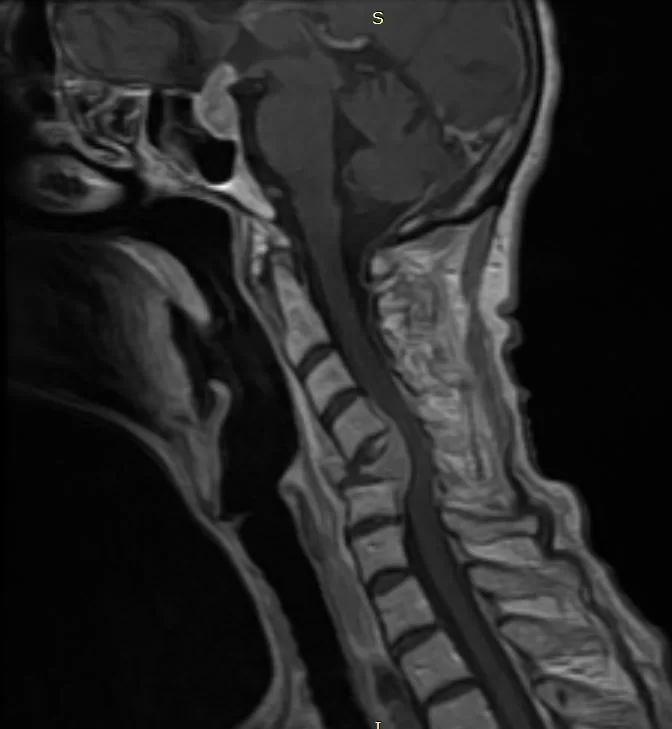

Ασθενής γυναίκα 61 ετών με σημαντική τετραπάρεση (αδυναμία άνω & κάτω άκρων) λόγω νεοδιαγνωσθείσας χωροκατακτητικής εξεργασίας (όγκος) στον Α5 σπόνδυλο, ο οποίος έχει διαβρώσει πλήρως το οστό και έχει προκαλέσει κάταγμα του σπονδύλου με αποτέλεσμα πίεση του νωτιαίου μυελού και σημαντική παραμόρφωση της σπονδυλικής στήλης.

Προεγχειρητικές Εικόνες (Μαγνητική Τομογραφία & Αξονική Τομογραφία)